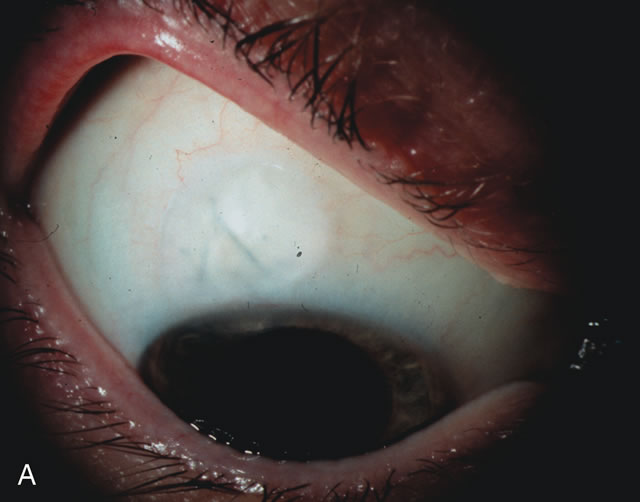

CATARACT EXTRACTION ALONE REDUCES IOP IN MOST EYES WITH ANGLE-CLOSURE GLAUCOMA

Uncomplicated cataract extraction substantially reduces IOP, along with the number of postoperative glaucoma medications in eyes with angle-closure glaucoma.146,147 When preoperative gonioscopy reveals PAS, along with adjacent areas of appositional closure, lens extraction alone in select cases may be a reasonable alternative to filtration surgery.148,149 Phacomorphic angle-closure disease due to enlargement of the lens with progressive angle crowding is eliminated following lens extraction. The width and depth of the anterior chamber angle in eyes with angle-closure glaucoma increases significantly after cataract extraction with IOL implantation and becomes similar to open-angle glaucoma and normal eyes.150,151 (Fig. 5). Combining phacoemulsification, IOL implantation, and limited goniosynechialysis is effective in the treatment of cataract and chronic angle-closure glaucoma.152 Phacoemulsification with implantation of a foldable IOL is more effective in reducing IOP and improving visual acuity than surgical peripheral iridectomy in eyes with acute angle-closure glaucoma.153

Fig. 5. Anterior chamber angle changes associated with lens extraction and PCIOL This 65-year-old Vietnamese woman has a long-standing history of chronic angle-closure glaucoma treated with laser peripheral iridectomy. The optic nerve demonstrated mild glaucomatous damage and IOP was moderately controlled on two antiglaucoma medications. The cataract was removed through temporal clear corneal phacoemulsification with foldable acrylic IOL. A. Symptomatic cataract in narrow-angle glaucoma eye with patent iridectomy. B. Intraoperative goniophotograph showing crowding of angle with increasing narrowness due to phacomorphic component. C. Intraoperative photograph showing temporal clear corneal approach with IOL in the capsular bag. D. Intraoperative goniophotograph demonstrating deepening of chamber angle following lens extraction. Proposed theories for IOP reduction following lens extraction with complete wound closure: